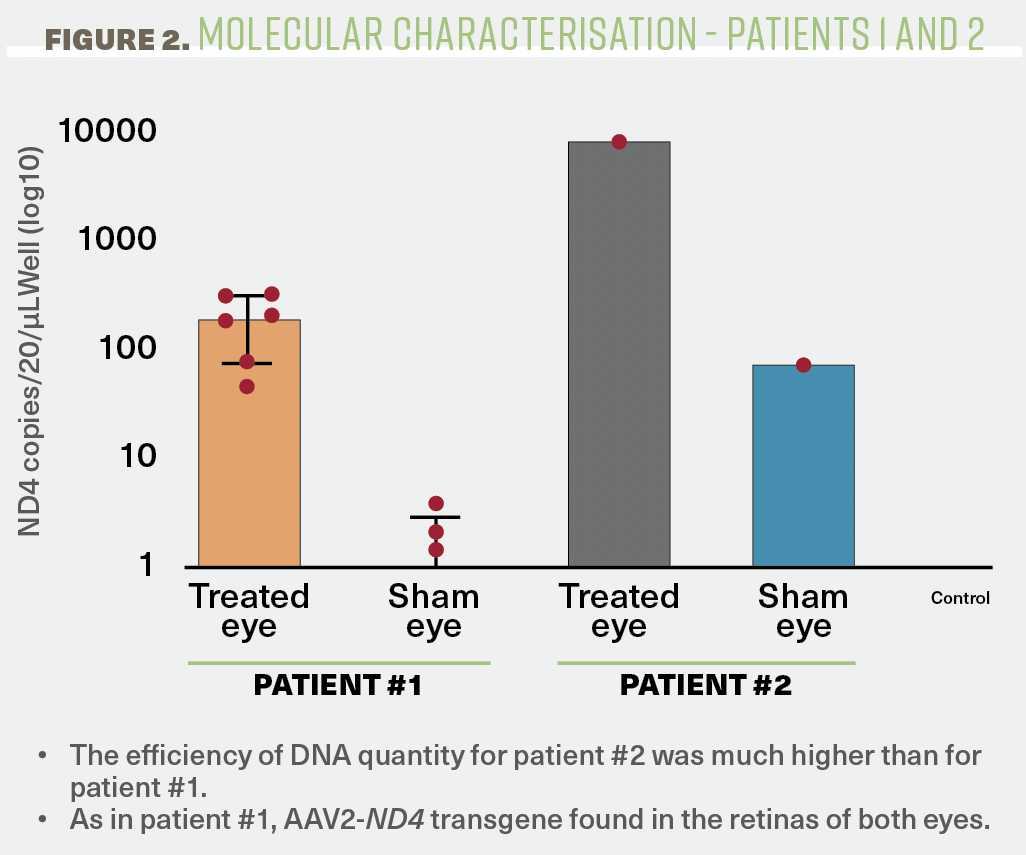

Commenting on the findings, the authors said, “The efficiency of DNA quantity for patient 2 was much higher than for patient 1. As in patient 1, AAV2-ND4 transgene was found in the retinas of both eyes.”

In patient 2, in contrast, there was no histopathologic evidence of persistent inflammation. However, similar to patient 1, AAV2-ND4 transgene was found in the retinas of both eyes and at about the same ratio of 200 (injected eye) to 1 (fellow eye) [Figure 2].

Figure 2. AAV2-ND4 transgene distribution in both eyes.